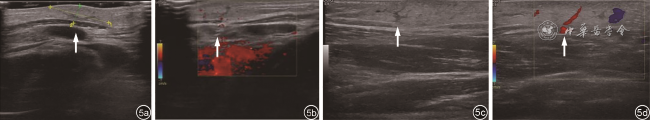

术后第2个月复查血清肿瘤标志物全套未见异常;骨髓穿刺髓象分析显示粒细胞比例减低,幼红细胞比例增高(图4)。超声复查:左腹股沟和左胸壁表皮及浅筋膜间隙各显示一个团块,直径分别为4.1、1.6 cm,无包膜,边界不清,内见细管状低回声,与术前左大腿包块声像图类似。CDFI:团块内见点状、条索状血流信号(图5)。超声提示:结合病史考虑皮下脂膜炎样T细胞淋巴瘤。

图5 左胸壁包块及左腹股沟包块超声图像。图a,b分别为左胸壁包块二维及彩色多普勒血流图像示皮下脂肪层内稍高回声区伴细管状低回声(图a箭头所示),其内可见点状及条状血流信号(图b 箭头所示);图c,d分别为左腹股沟包块二维及彩色多普勒血流图像示皮下脂肪层内稍高回声区伴细管状低回声(图c箭头所示),其内可见点状及条状血流信号(图d箭头所示)